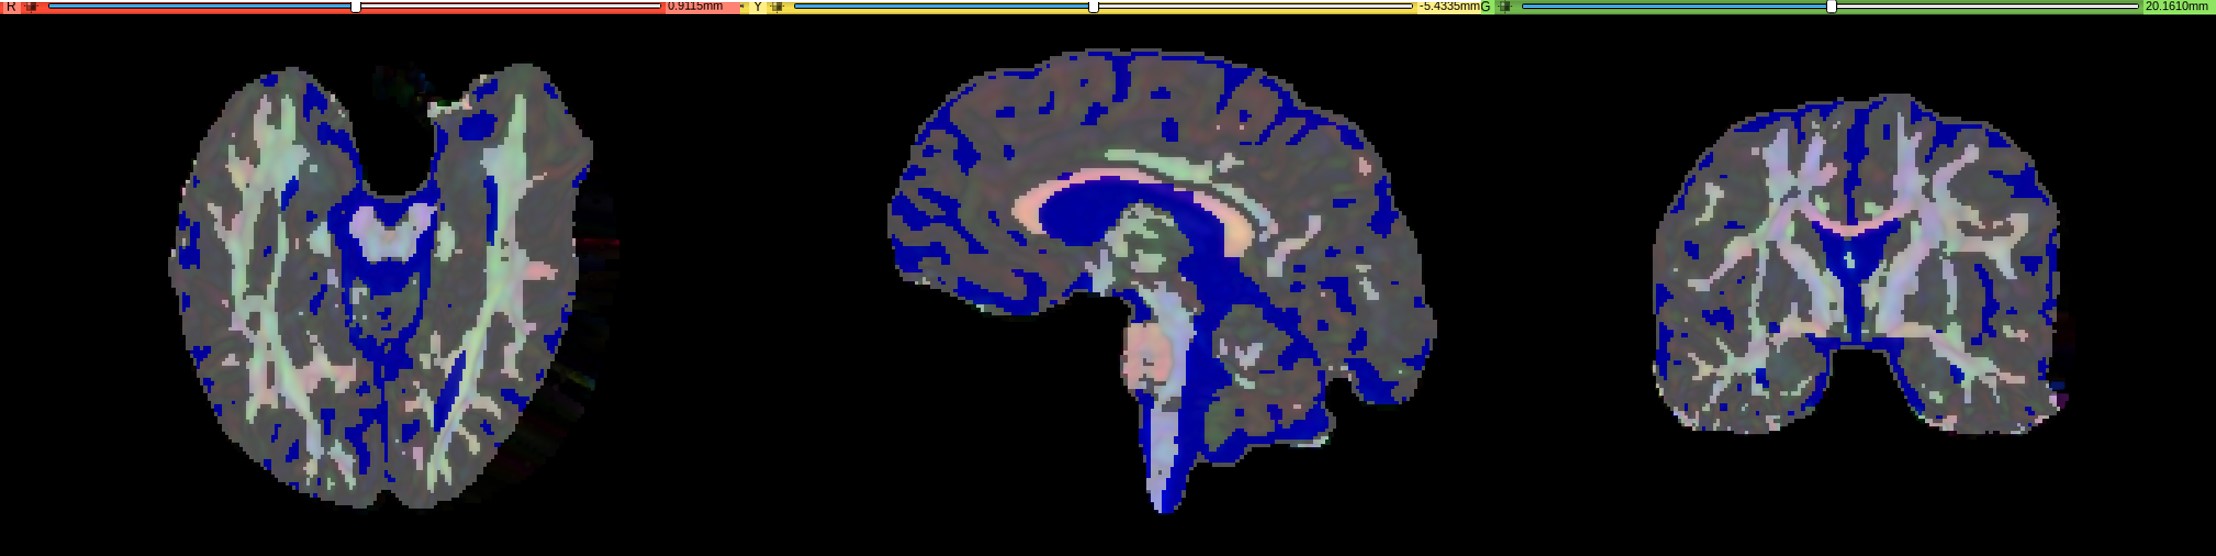

Refer to caption

Figure 2: Results of DTI based image segmentation for a deformed DTI image. Grey represents grey matter, dark blue represents CSF and remaining represents white matter. The segmentation of the tissues (white matter, grey matter and CSF) is overlaid with the DTI image.

2.2.1 Segmenting brain tissues using diffusion tensor imaging:

A fuzzy c-means clustering algorithm is used to classify brain tissues using diffusion tensor imaging (DTI) [23]. In the first step, mean diffusivity is used to separate the cerebrospinal fluid (CSF) from the rest of the brain. In the second step, fractional anisotropy is used to separate the white matter (WM) from the gray matter (GM). The results of DTI based image segmentation are shown for a deformed DTI in Fig 2.